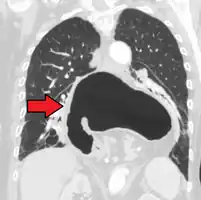

A hiatal hernia as seen on CT